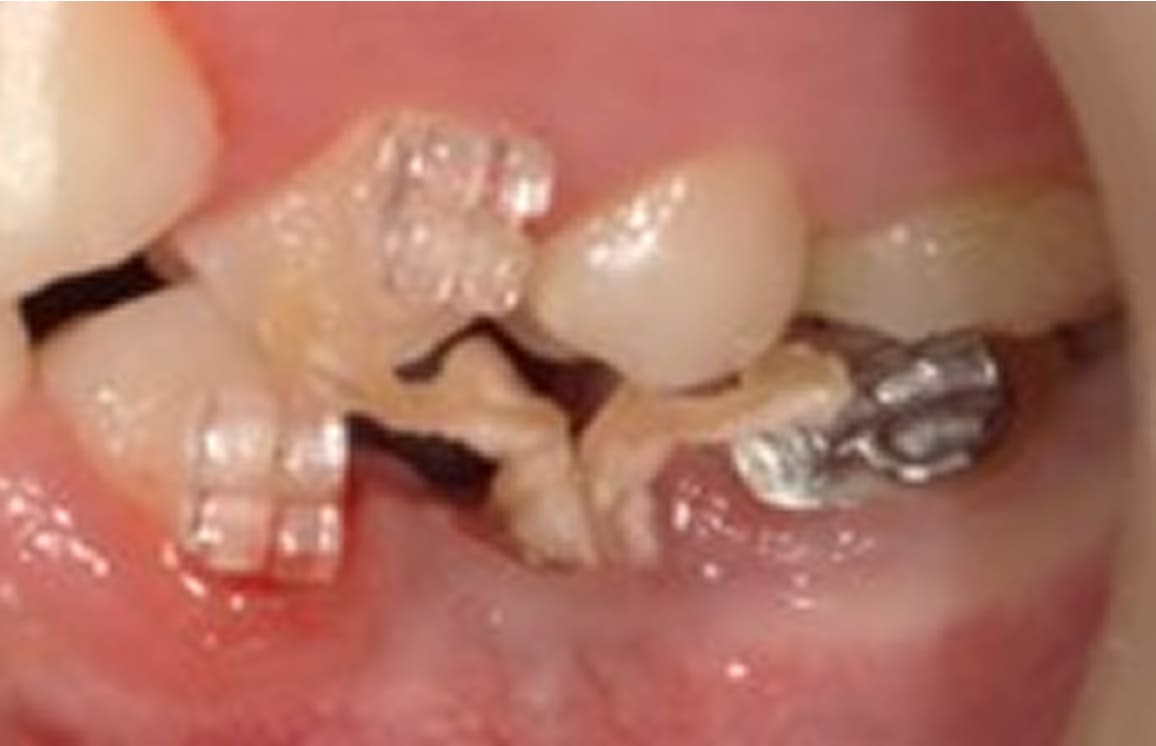

歯を抜かない治療(C4)

不幸にも、虫歯が進行して骨に埋まっている部分の歯(歯根)まで細菌感染が起こってしまった場合(C4)、通常では抜歯が適応治療になります。 しかし、歯根まで虫歯が進行してしまっている場合の多くは痛みが無いのも特徴です。 特に痛みも無いのになんで歯を抜かなければならないかとお思いの患者様も多くいらっしゃいます。 生物学的・医学的には抜歯が適応であったとしても、患者様のご希望と、精密検査の結果から、当院では歯を抜かずに温存する治療も行っております。 もう歯がほとんど残っていないから歯を抜かなければならないと諦めていらっしゃる患者様も、ぜひ一度当院にてご相談、検査をさせて下さい。